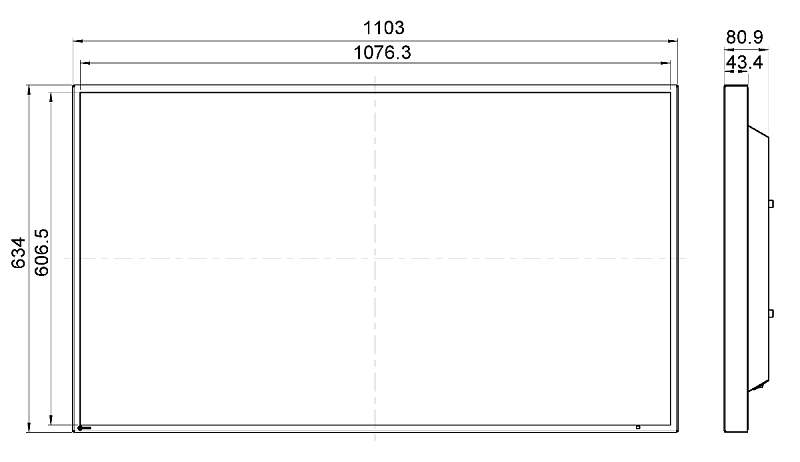

LX491W

LX491W

This 49” widescreen monitor is ideally suited for viewing medical images under OR conditions. Numerous input and output signals, image combination capabilities, and gamma models pre-calibrated at the factory enable its use within the widest range of applications. With its fan-free design and water-tight, easy to clean front, the monitor is perfectly suited for sterile hospital environments.